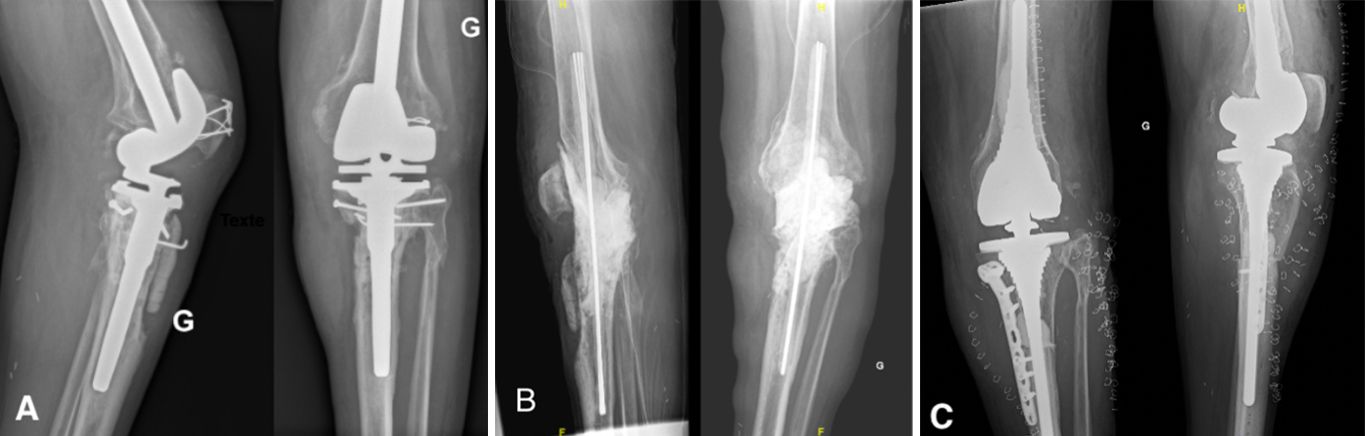

Antibiotic-impregnated cement spacers can be either static (non-articulating, block spacer) or dynamic [10]. Static spacers consist of a single block of cement inserted between the femur and the tibia (Case 1.B, 2.B, 3.B). It is non-articulating, fills the joint space and constitutes a temporary knee arthrodesis keeping the knee in full extension. This temporary immobilization leads amongst other things to joint stiffness and exposure difficulties at the time of reimplantation [9, 22, 23]. This increases the difficulty of prosthesis reimplantation and is associated with poorer clinical outcomes such as stiffness.

- Major bone loss, which is associated with a high risk of fracture, as well as a lack of fixation for a dynamic spacer (Cases 1-3).

Step 3: Making the static spacer

The firsts step is the fashioning of a rigid rod of cement reinforced by Kirschner wires to reduce the very high risk of spacer fracture. 3-4 wires of 2 mm diameter should be used and coated with high-viscosity antibiotic cement. When the mixture starts to solidify, it is molded manually by the surgeon (Fig.2).

The length must be long enough to have at least 6 cm of rod in each femoral and tibial canal, plus the length of the joint space to bypass the joint and be stable and strong enough. Once set, this rod, marked at its center, is introduced back and forth into the femoral and tibial canals until the center mark is at the midpoint of the joint space (Fig.3). We usually use 1 cement package of 40 g for this rod.

Next, the whole spacer is prepared using high-viscosity antibiotic cement. We use cement with Gentamycin and add crystalline Vancomycin, 1g per cement package. The Vancomycin should be added to the cement before being added to the liquid monomer [13]. If the Vancomycin is added later, the mixing is inconsistent due to poor dissolution and risks unequal diffusion into the soft tissues. We advise adding methylene blue to the preparation. We usually use 1 mL, added just at the start of mixing, to obtain a homogenous blue paste (Fig.4). The methylene blue is added to the cement to provide easy discrimination between native bone and cement and facilitate cement removal during the second stage of surgery [25].

The spacer should fill the joint space to maintain the native leg length. 2 minutes after the second cement mixture, the joint is opened with traction on the leg in extension to fill any bone defects and the joint space with cement. The size of the spacer should be appropriate but not too large to avoid excessive skin tension during wound closure. This second cementation stabilizes the construct and prevents spacer migration (Fig.5). The joint capsule, subcutaneous tissues, and the skin are closed in layers.